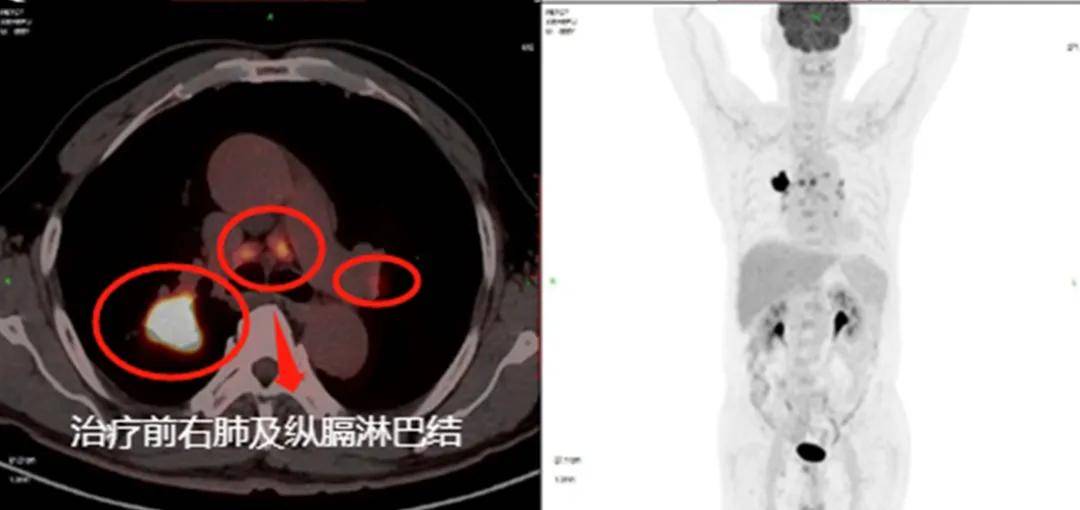

来到科室后,谢叔神情沉静,却掩不住眼底的焦虑。为了明确肿瘤的分期和扩散范围,医疗团队为他安排了全身PET-CT检查。报告出来后,连医生都忍不住皱了眉——右上肺的病灶约29×22毫米,双侧肺门、纵膈、右锁骨上区的淋巴结都有转移灶,左肾上腺和多处骨骼也发现了代谢活跃的病变。也就是说,癌细胞已经不只是“在肺里”,而是全身多发转移。

治疗前影像

谢叔的治疗过程,是精准、清晰与稳健的结合。初诊时的PET-CT准确揭示了右上肺病灶及多处转移,为医疗团队及时确立全身性治疗目标奠定了基础,避免因低估病期而错过最佳时机。确诊后,治疗路径始终遵循“化疗降负荷—免疫维持防复发”的主线:前期化疗迅速控制病情,后期PD-1维持持续激活免疫监视,使治疗过程有节奏、有方向。整个疗程中,医疗团队根据体能精确调控剂量,保持疗效与耐受的平衡;并通过影像与实验室双重监测,确保疗效可控、安全可防。当出现病毒性肺炎或轻度内分泌异常时,医疗团队迅速应对、及时干预,避免了风险扩大。从最初布满高代谢灶的PET-CT,到免疫维持期几乎清透的肺野,谢叔的康复历程充分印证:分期要准,路径要清,节奏要稳,监测要勤,反应要快——这是他重获新生的关键所在。